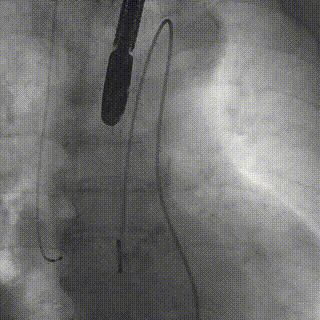

释放

后扩前

后扩

最终工作位置

术中及术后未出现相关并发症,瓣膜植入位置完美,患者症状得到明显改善,手术圆满完成。